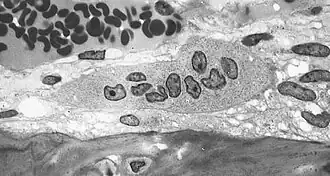

Osteoclasto (do grego para "osso" (Οστό) e "quebrado" (κλαστός)) é uma célula móvel, gigante e extensamente ramificada, com partes dilatadas, e é multinucleada. Os osteoclastos foram descobertos por Kolliker em 1873.[1]

Nas áreas de reabsorção de tecido ósseo encontra-se porções dilatadas dos osteoclastos, colocadas em depressões da matriz escavadas pela atividade dos osteoclastos e conhecidas como lacunas de Howship. Os osteoclastos tem citoplasma granuloso, algumas vezes com vacúolos, fracamente basófilo nos osteoclastos jovens e acidófilos nos maduros.

Estas células se originam de precursores mononucleados provenientes da medula óssea que, ao contato com o tecido ósseo, unem-se para formar os osteoclastos multinucleados. A superfície ativa dos osteoclastos, voltada para a matriz óssea, apresenta prolongamentos vilosos irregulares.

A maiorias desses prolongamentos tem a forma de folhas ou pregas que se subdividem. Circundando essa área com prolongamentos vilosos, existe uma zona citoplasmática, a zona clara, pobre em organelas porém com muitos filamentos de actina. A zona clara é um local de adesão do osteoclasto com a matriz óssea e cria um microambiente fechado, ácido (H+), colagenase e outras hidrolases que atuam localmente digerindo a matriz orgânica e dissolvendo os cristais de sais de cálcio.

Morfologia

Os osteoclastos são células muito grandes, que tem cerca de 40 micrómetros de diâmetro. Possuem vários núcleos e são responsáveis pela destruição do osso. Quando a membrana celular dos osteoclastos entra em contato com a matriz óssea formam-se prejecções que constituem um bordo pelo qual entram íons hidrogênio para assim ser produzido um meio ácido que provocará a descalcificação da matriz óssea. Nos osteoclastos o retículo endoplasmático rugoso é escasso, e o complexo de Golgi é extenso.[2][3]